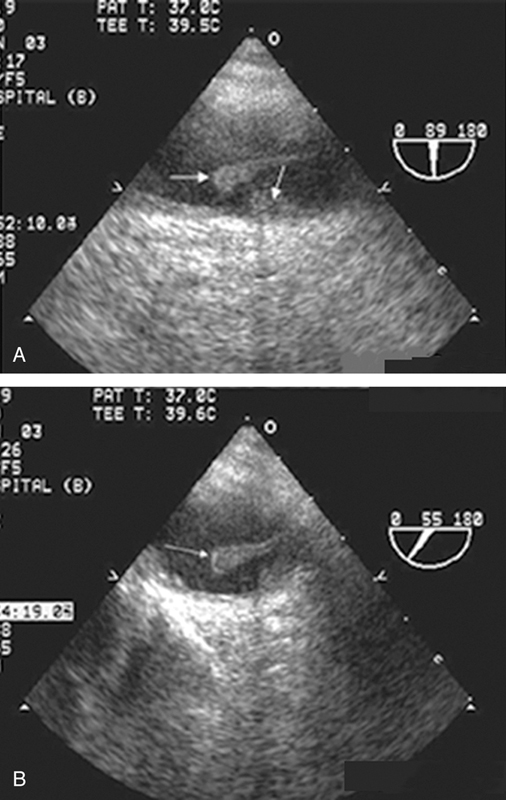

فحوصات تشخيصية لبعض امراض القلب والشرايين التاجية